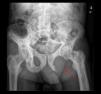

We report the case of an 82-year-old male patient diagnosed 10 years prior with Paget's disease and polyostotic involvement. Relevant history showed atrial fibrillation and chronic heart failure. He came to the immediate care clinic (UCAI) due to fatigue, anorexia and edema of the lower extremities, which had been present for 15 days. The systems review referred pain in the left ischiopubic region since 6 months before, which had been increasing and appeared both at rest and with exercise. He was admitted for heart failure treatment and study of the origin of pain. Physical examination showed pale skin and mucous membranes, irregular cardiac auscultation with systolic aortic murmur, decreased breath sounds on widespread lung auscultation, pitting edema up to the root of both lower limbs and pain on movement and decreased function of the left hip joint. On rectal examination there were no masses but only with remnants of normal stool. Complementary tests showed hemoglobin of 9.5g/dl with normal mean corpuscular volume and hemoglobin, CRP: 21.2mg/dl (0.2–0.8), fibrinogen: 722mg/dl (200–400), glomerular filtration rate: 120mm (1–15), alkaline phosphatase, 155U/l, iron: 23.6mg/dl (50–150) transferrin: 155mg/dl (300–360), ferritin: 1144mg/l (50–350), saturation index: 12% (20–40), soluble transferrin receptor: 7.88mg/l (2–4), tumor markers were normal. The chest X-ray showed bilateral pleural effusion and small lesions consistent with Paget's disease in both shoulders and the fifth left rib. Pelvic X-ray showed multiple lesions consistent with Paget's disease and a larger lytic image on the left ischium (Fig. 1). A bone scan was performed which showed images compatible with Paget's disease and no uptake in the left ischium (Fig. 2). A thoraco-abdominal CT-scan revealed a large pelvic mass with lobulated contours and foci of calcification that destroyed the left ischium and acetabulum measuring 12cm×12cm×16cm (Fig. 3). Suspecting a bone neoplasm added to Paget's disease the patient underwent an iliac bone biopsy which was consistent with undifferentiated pleomorphic high grade non osteogenic sarcoma, vimentin positive, with coexpression of CD-68 and low expression of actin and desmin. The patient outcome was unfavorable, suffering great malaise and difficulty controlling the pain, he decided to initiate treatment with radiotherapy for symptomatic control fundamentally. Finally, the patient died a week after the pathological diagnosis.